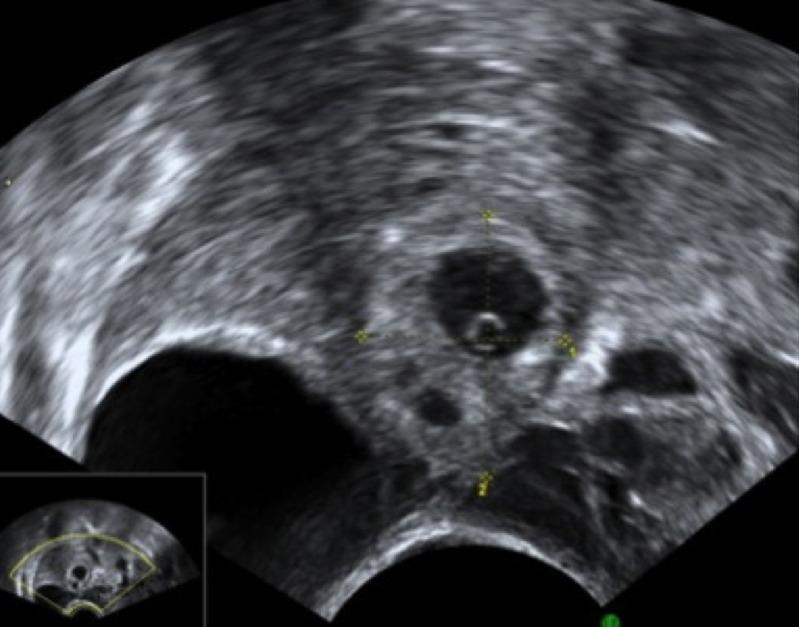

Retrospective cohort study. Non- viable tubal ectopic pregnancy was diagnosed on transvaginal ultrasound. If initial serum β hCG was less than 5000 IU/L and patients were asymptomatic, expectant management was offered. Patients underwent serial β hCG measurements until serum β hCG was less than 20 IU/l, or the urine pregnancy test was negative.

回顾性队列研究。经阴道超声诊断为不可行的输卵管异位妊娠。如果初始血清β -hCG低于5000 IU/L且患者无症状,则给予期待治疗。患者进行β -hCG系列测量,直至血清β -hCG低于20 IU/l或尿妊娠试验为阴性。